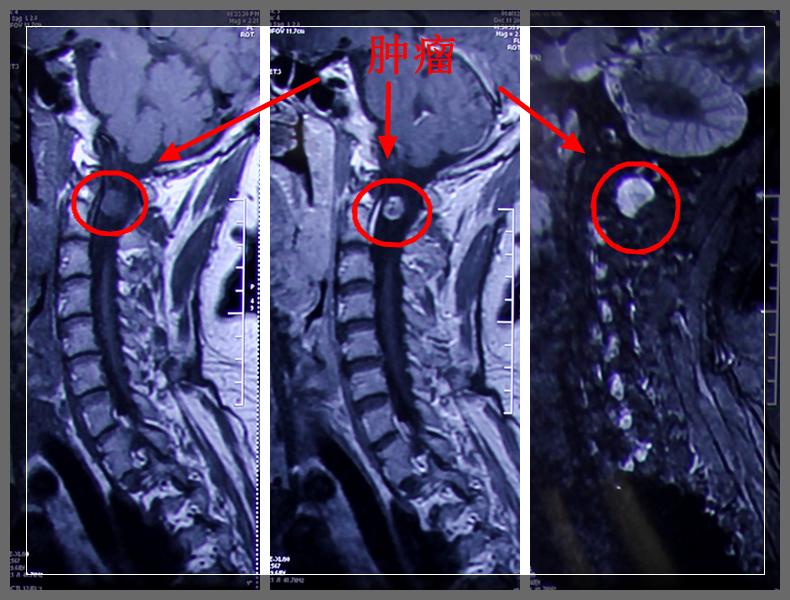

临床上,椎管内神经鞘瘤的诊断多需借助影像学检查,较常用的有椎管造影、腰椎穿刺、脊柱平片、CT及核磁共振(MRI)。其中,MRI是目前最精确的影像学检查方法(肿瘤在MRI T1加权图像上呈髓外低信号瘤灶,在T2加权图像上呈高信号瘤灶;增强扫描:实体性肿瘤呈均匀强化,囊性肿瘤呈环形强化,少数肿瘤呈不均匀强化。另视肿瘤所在解剖层次不同,出现相应的脊髓移位)。

(颈1-2神经鞘瘤)